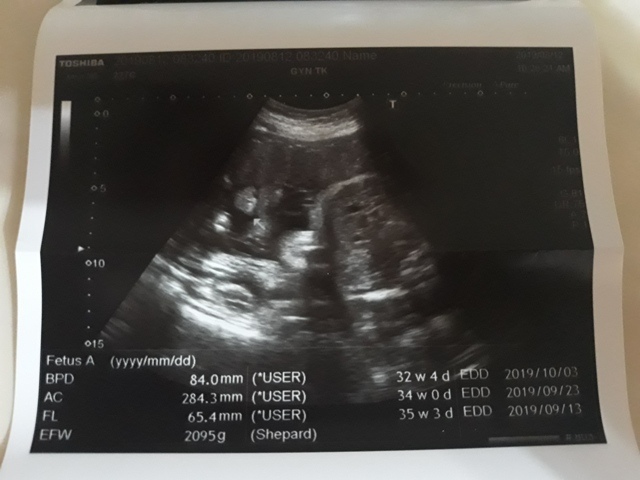

和小純去澄清醫院產檢

早上和小純去清澄做產檢,我們大約十點左右到達,在現場等了半小時之後,輪到我們看診了。我們所關心的胎位不正問題,今天檢查的結果,胎位仍然不正(其實從這幾天小飛的胎動位置來看,感覺腳仍然是在下面)。

此時關醫師也發現羊水量不足,只有2.5(關醫師沒說單位,但我後來上網查,應該是羊水深度2.5cm),要多補充水份。並叫我們下星期再來檢查(原本是兩個星期檢查一次的),如果羊水還是不足的話,就會提早讓小飛生產。

其實前陣子胎位不正的問題,讓我們有思考到有可能會剖腹產,今天又出現了羊水不足的問題,還有可能得被迫提早剖腹產,只能請小純這陣子多補充水份,希望能增加羊水量。

近九次產檢資料統計(5月22日是高層次超音波)↓

| 2019年08月12日 | 84.0mm (5%) | 284.3mm (7%) | 65.4mm (10%) | 2095g (20%) | 未量測 |

| BPD:胎兒頭骨橫徑 AC:胎兒腹圍的長度 FL:胎兒大腿骨的長度 EFW:胎兒的體重 括弧內百分比為較上次產檢的成長比例 | |||||